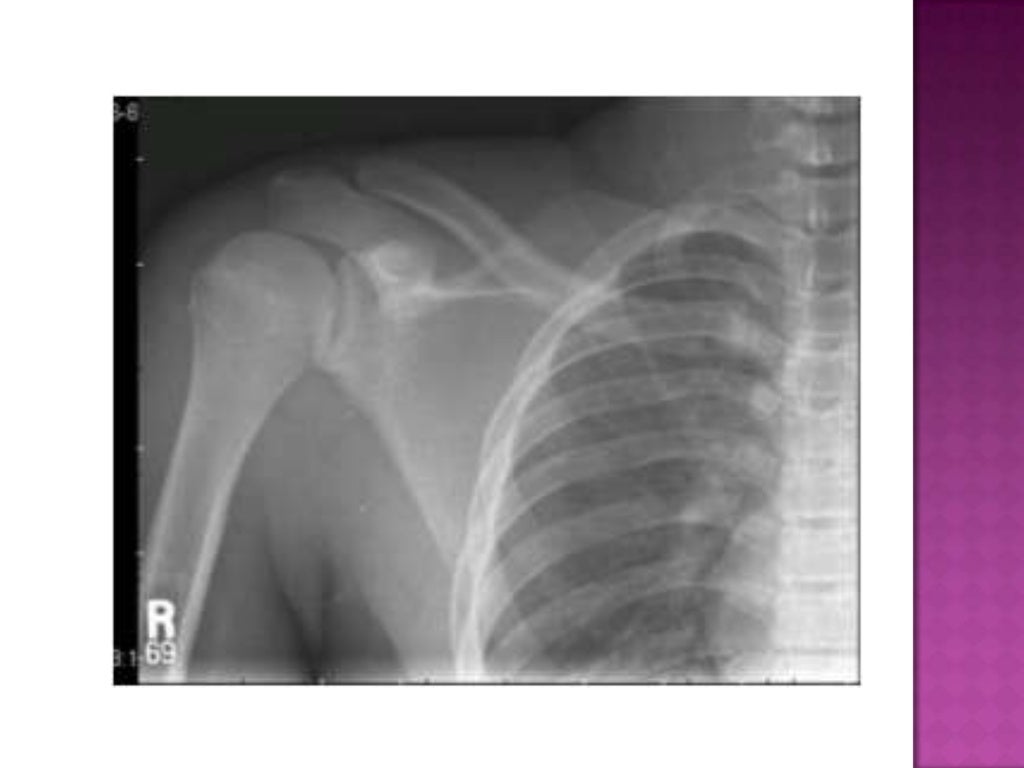

Anteroposterior radiograph of the left arm showing normal shoulder Which Joints Are Included On A Humerus Radiograph See osteosarcoma of the humeral. Articulates with the glenoid cavity of the scapula. Rotation of the humeral head. Lateral radiograph of the humerus with labels. See a charcot joint of the shoulder here. Above images from wikiradiography (wetpaint) here. However, it can also be taken in the supine position in the. Ideally, a shoulder radiograph series will provide adequate views. Which Joints Are Included On A Humerus Radiograph.